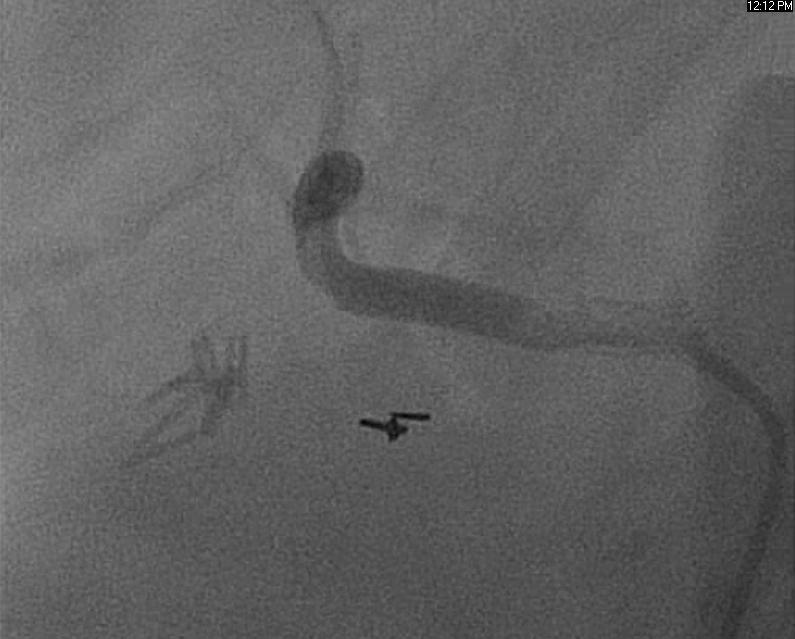

A 55-year-old gentleman with a history of coronary artery disease, diabetes and mesenteric ischemia status post celiac trunk stent placement presented to clinic with abdominal pain. Initially improved in the months following stent placement, now (almost two years later) he is complaining of postprandial left upper quadrant pain, vomiting and a fear of eating. He was scheduled for elective angiography, which revealed a 90{8ceaa46882e4d49283ff23b35262537230ad541262f55a031ead545e66522058} in-stent restenosis in the celiac trunk (Fig 1).

Sequential drug-eluting stents were placed and post-dilated with a good result (Fig 2, 3).